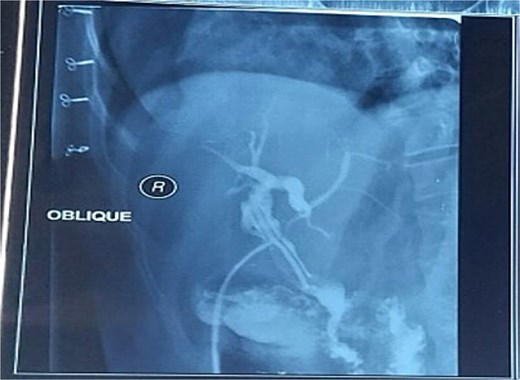

The postoperative course was uneventful, and the patient was discharged on postoperative Day 5. Three weeks later, a T-tube cholangiogram (Fig. 2) confirmed complete stone clearance, after which the T-tube was removed.

Postoperative T-tube cholangiogram confirming complete stone clearance with no residual filling defects in the CBD.